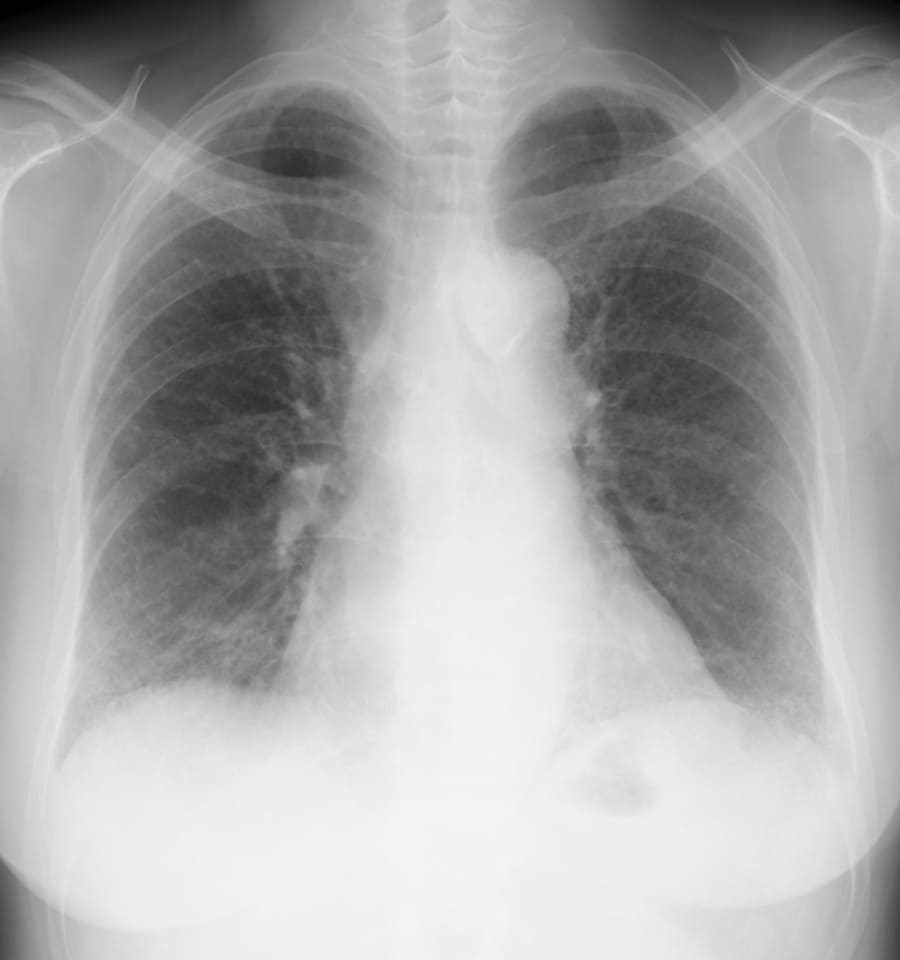

DATA 1| X 線検査結果

画像にマウスオン(またはタップ)すると虫眼鏡で拡大できます

できます

気管支血管束に沿う均質な網状変化と重なるすりガラス影。

一部、胸膜下をスペア。fNSIP+UIP混在。

肺動脈は太めで食道の拡張あり、膠原病肺の疑い。